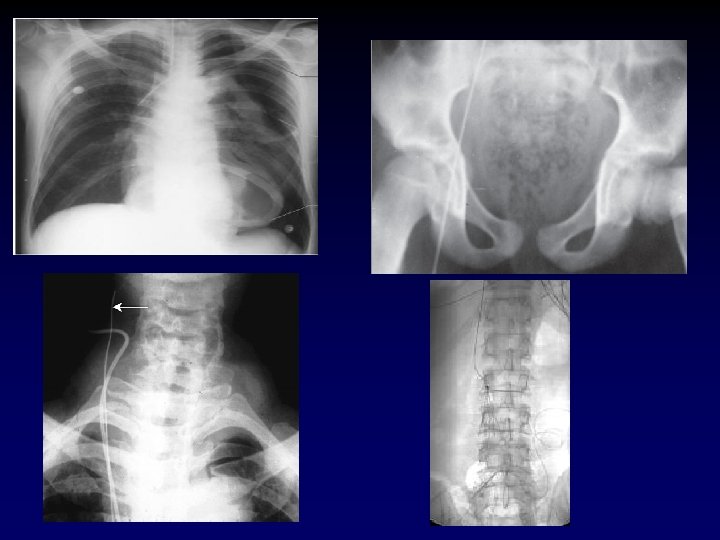

Case Presentation • 25 year old male presents s/p single stab wound to the left chest. He clearly smells of alcohol and is lethargic – responding only to painful stimuli. Field vitals are P 150, BP 80/palp, Resp 35. • What’s the plan? ?

Tube Thoracostomy • Indications: − Hemothorax/Pleural effusion − Pneumothorax − Note for tension pneumothorax first tx should be 14 or 16 gauge angiocath in 2 nd intercostal space in midclavicular line. • Anatomy: • 5 th intercostal space in the anterior axillary line (at the level of the nipple). • Measure tube from insertion site to apex of lung.

Case Presentation • Now that the chest tube is draining the hemopneumothorax, the patient’s pressure drops to 60/palp • Help? • The patient has bilateral track marks from history of IVDA.

Central Venous Access • Indications – CVP monitoring – TPN – Long-term infusion of drugs – Inotropic agents – Hemodialysis – Poor peripheral access

Central Venous Access • Vein sites – Femoral – Subclavian – Internal jugular • Contraindications – Vein thrombosis – Coagulopathy or thrombocytopenia

Case Presentation • Now with a femoral cordis in place, the patient receives 2 liters of LR with an improvement in vitals. He has 800 cc of blood drained from his left chest. • Is he adequately resuscitated? Over? Under?